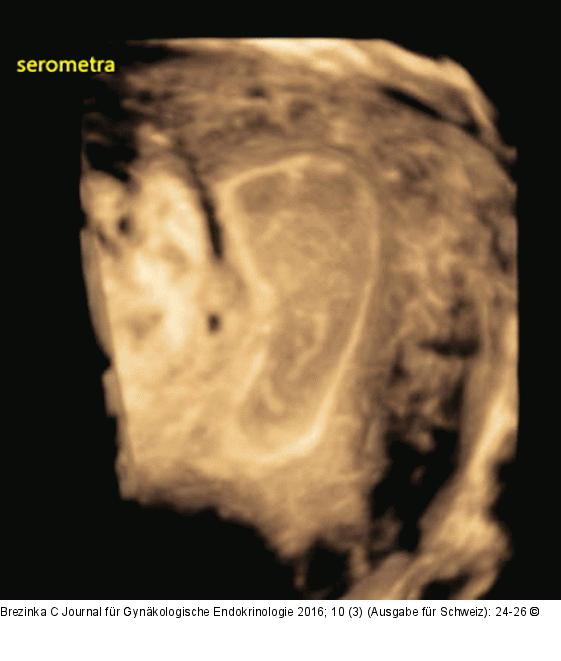

Abbildung 3: Ultraschall-Serometra Selber Fall wie Abbildung 2 mit 3D-Ultraschall: Zwischen einem dünnen, echodensen Randsaum aus Endometrium hat sich eine Ansammlung von Flüssigkeit mit länglichen, echodensen Strukturen gebildet. Der Stimulationszyklus wurde abgebrochen. |

Selber Fall wie Abbildung 2 mit 3D-Ultraschall: Zwischen einem dünnen, echodensen Randsaum aus Endometrium hat sich eine Ansammlung von Flüssigkeit mit länglichen, echodensen Strukturen gebildet. Der Stimulationszyklus wurde abgebrochen. |